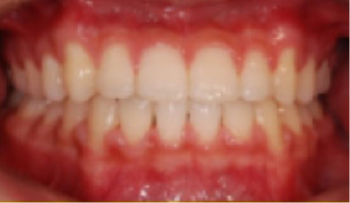

교정 치료 Before&After

• 상악 전돌(돌출) 위턱이 앞으로 나옴.

Before

After

• 총생(Crowding) 치아가 삐뚤게 남.